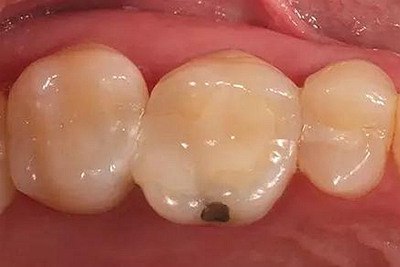

步骤1 原始状况

16牙位牙齿牙合面观.

牙齿经过根管治疗且充填修补,需要重新修复。